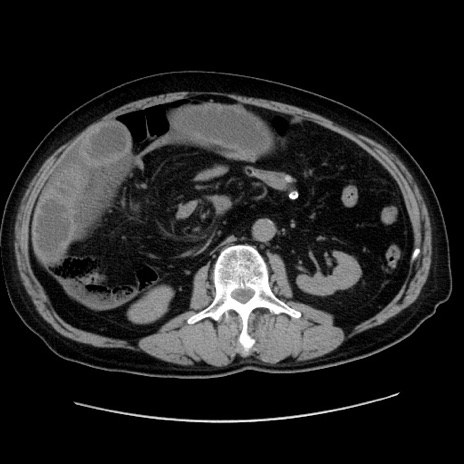

症例30(横断像)

【症例】80歳代男性

【主訴】臍周囲痛

【現病歴】約6時間前から臍下部痛が出現。次第に腹部膨隆・背部痛も生じてきたため来院。背部痛の場所は変化しない。

【既往歴】腎盂腎炎

【身体所見】意識清明、BT 36.3℃、BP  131/87mmHg、P 87bpm、SpO2 100%(RA)、臍周囲自発痛・圧痛あり、反跳痛なし、自発痛部位に一致して板状硬あり、腹部膨隆、腸雑音減弱、CVA tenderness両側陰性。

【データ】WBC 19600、CRP 0.33

冠状断像